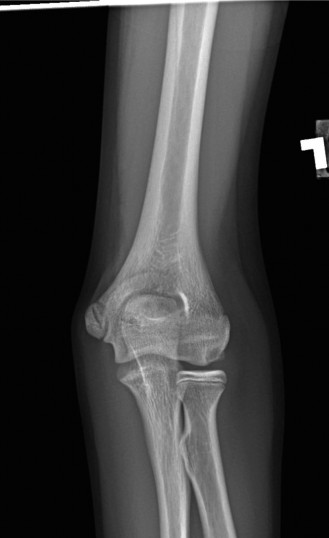

Understand the radiographic findings seen in patients with valgus overload? Identify indications for operative intervention? CASE 41 Dr. Min Lu A 14-year-old baseball pitcher presents to the office with left throwing elbow pain for the past two months when he throws or lifts weights. Examination reveals lateral joint line tenderness with no detectable effusion and full range of motion without crepitation. Moving valgus stress test does not elicit pain. His elbow radiograph is shown below (Fig. 2–111).

Figure 2–111

The correct answer is (E). This patient has osteochondritis dissecans (OCD) of the capitellum. He has not undergone any conservative treatment. Stable, nondisplaced lesions can heal spontaneously with rest and discontinuation of throwing. Surgical treatment is reserved for unstable lesions or loose bodies. This patient’s

The correct answer is (E). Fragmentation and separation of the capitellum can be seen with osteochondritis dissecans or Panner’s disease, with the distinguishing factor being the amount of capitellar involvement. Osteochondritis dissecans involves a focal articular defect, whereas Panner’s disease involves the entire capitellum. Olecranon osteophytes are encountered with valgus extension overload. Loose bodies may be seen in later stages of osteochondritis dissecans. Medial epicondyle avulsion fracture is a rare cause of acute elbow pain in skeletally immature athletes and is treated according to amount of displacement. Fragmentation and separation of the medial epicondyle is the characteristic radiographic finding of little league elbow (see Fig. 2–118). Previous studies have found separation or widening of the physis in over 50% of players while fragmentation occurred in roughly 20%.

Figure 2–118 Medial epicondylar separation seen in little league elbow. Objectives: Did you learn...? Recognize chronic overuse injuries in adolescent athletes? Manage a patient with little league elbow?